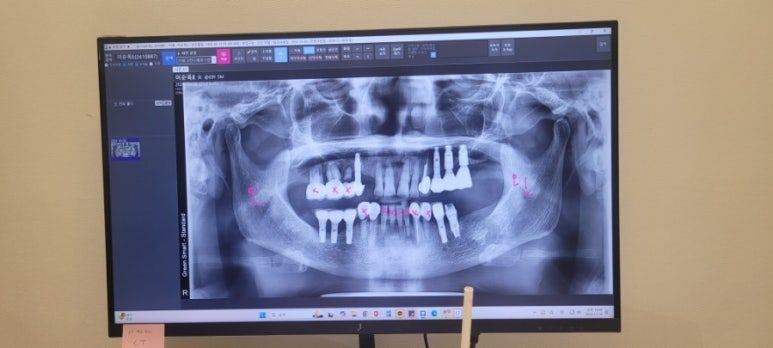

엄마는 현재 임플란트도 잇몸건강 악화로 흔들거려서 다 발치해야하고, 잇몸 이식도 해야 한다고 했다.

앞니가 다 썩어서 치료가 시급하고 올해가 국가 지원금 마지막 해라 치료하러 잘 오신거라고 했다.

3.jpg

엄마는 총 10개 발치하시고, 윗니 4개 식립, 아랫니 4개 식립, 7개 브릿지로 진행해서 총 300만원 견적이 나왔다.

선금 30만원

식립시 170만원

상학동거상술시 110만원

본뜨기시 90만원

미용상 틀니는 10개 발치하면 미관상 좋지 않으니 외출시 끼는 용도고 15만원이라고 했다.